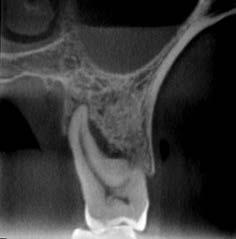

Der Patient wurde zur chirurgischen Entfernung des mesial verlagerten impaktierten Weisheitszahns im rechten Unterkiefer überwiesen. Mit dem 3D R100 wurde ein DVT erstellt, um den Abstand zwischen Wurzel und Nerv zu bestimmen. Die sagittale und koronale Ansicht zeigten den Verlauf des rechten Mandibularkanals durch die Wurzeln des dritten Molaren im rechten Unterkiefer und die Verschmälerung der lingualen Kortikalisschicht.